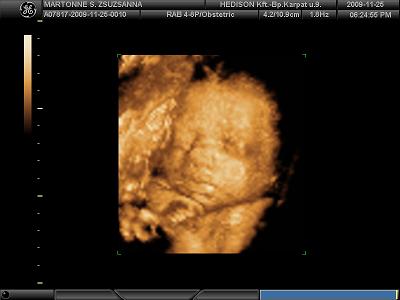

Köszönöm a képeket!!!!!

Tenci jól eltalálta, tényleg Jolie-s szája van Tominak!

És ha még Brad Pittre is fog hasonlítani............!!!!!!!!